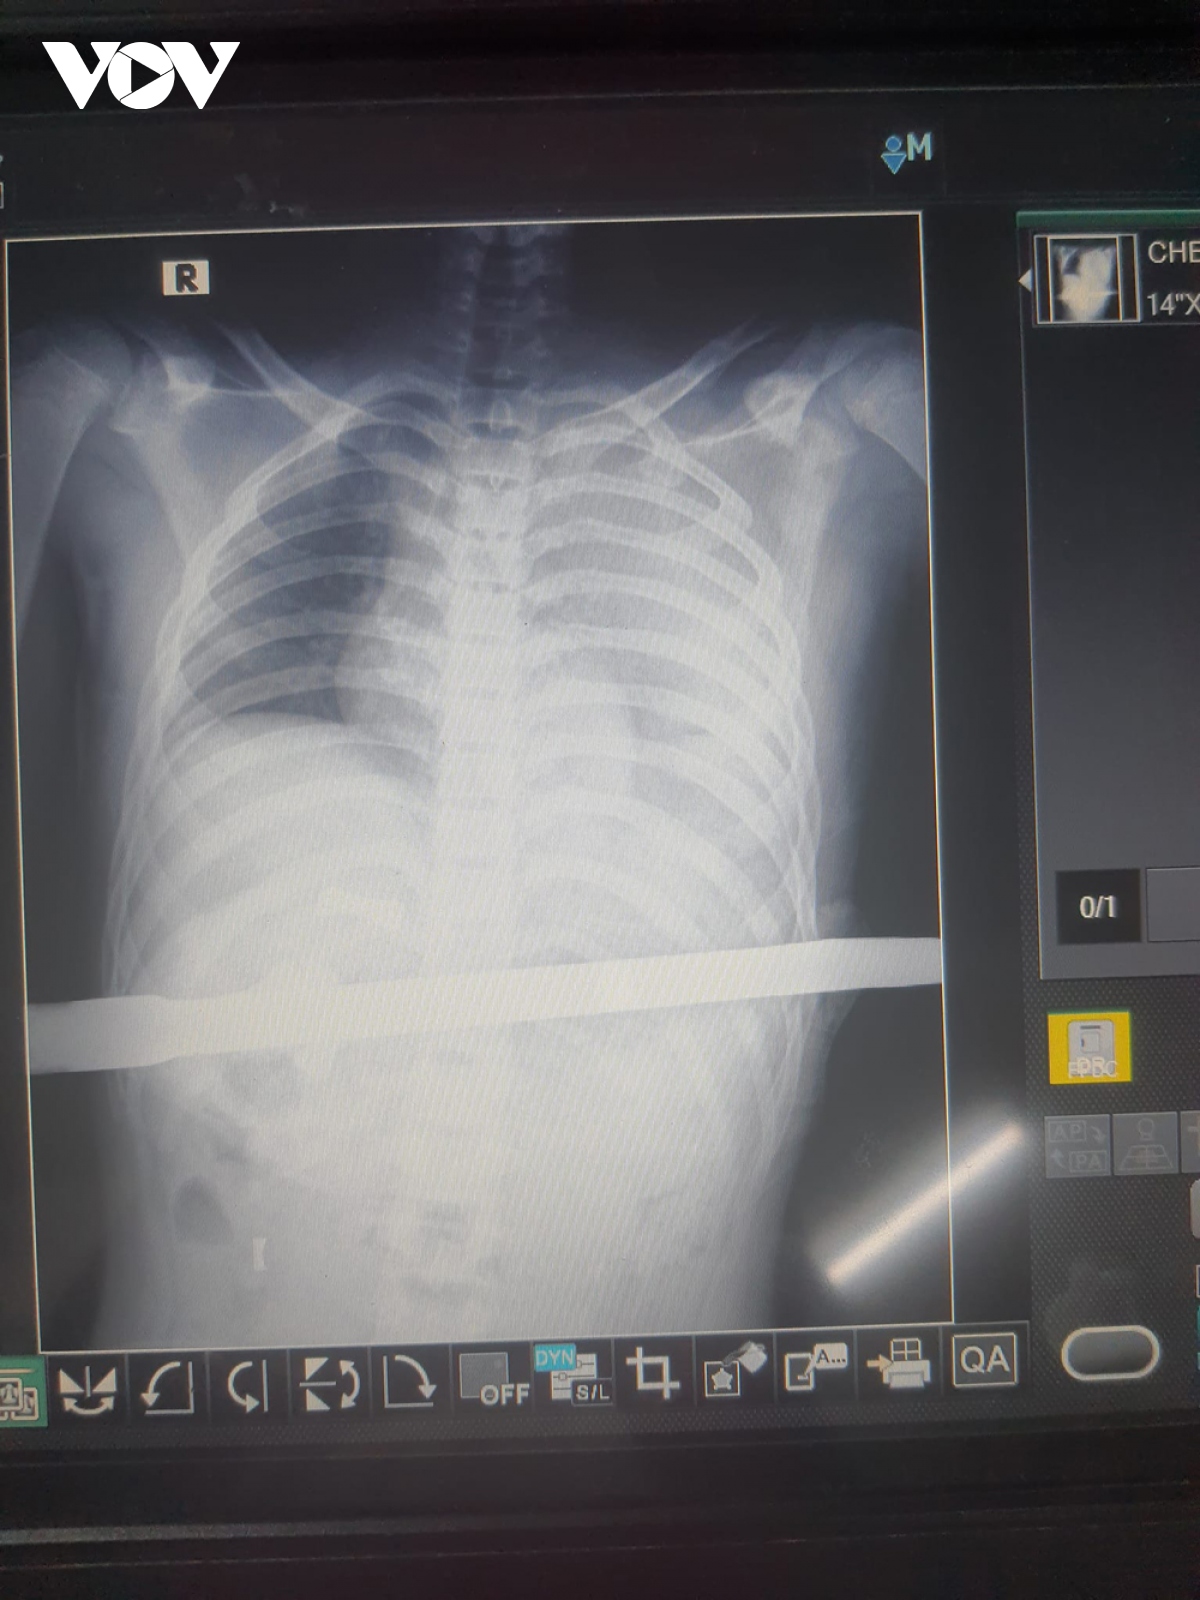

Theo thông tin ban đầu, vào khoảng 20h30 ngày 13/12, Bệnh viện Đa khoa tỉnh Bình Dương tiếp nhận bệnh nhân Đ.D nhập viện trong tình trạng choáng nhẹ, vết thương do lưỡi dao cạo mủ cao su đâm xuyên từ giữa ức đến ngực trái. Lưỡi dao cạo mủ vẫn còn dính với đoạn tay cầm bằng sắt dài khoảng 1m.

Kết quả siêu âm, bệnh nhân có tràn máu ổ bụng và màng phổi với dị vật xuyên thấu bụng ngực. Bệnh nhân được bác sĩ hồi sức tích cực, truyền máu và tiến hành phẫu thuật. Quá trình phẫu thuật, các bác sĩ phát hiện lưỡi dao xuyên thủng gan trái, dạ dày và cơ hoành. Hơn 2 giờ thực hiện ca phẫu thuật, bệnh nhân qua cơn nguy kịch và tiếp tục được các bác sĩ theo dõi hồi sức.